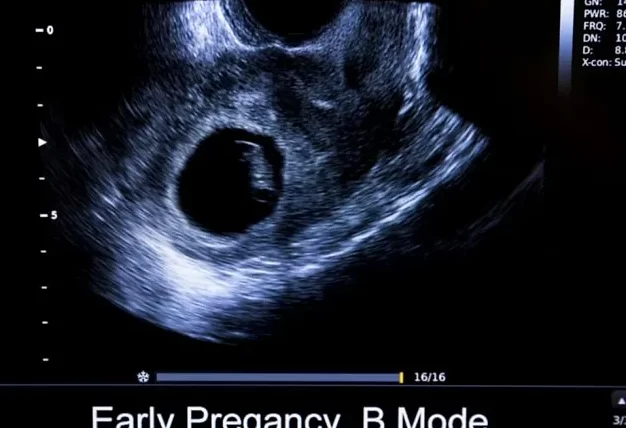

CRL significa Longitud Cabeza Nalgas – la distancia medida desde la parte superior de la cabeza hasta las nalgas de un embrión (hasta la 8va semana después de la fecha de concepción) o un feto (8-14 semanas de embarazo).

Realizará un examen de ultrasonido, encontrará el CRL y lo comparará con la tabla de longitud cabeza-nalgas; y

La calculadora de longitud céfalo-caudal (CRL) es una herramienta útil utilizada para medir el crecimiento fetal durante el embarazo. La medida de la longitud céfalo-caudal se toma desde la coronilla de la cabeza hasta el cóccix y se utiliza para estimar la edad gestacional y el tamaño del feto.

Para obtener una medición precisa de la CRL, es importante seguir las instrucciones cuidadosamente y asegurarse de usar equipos de ultrasonido de alta calidad. Además, es crucial comparar los resultados con estándares de crecimiento fetal establecidos para interpretar correctamente los datos obtenidos.